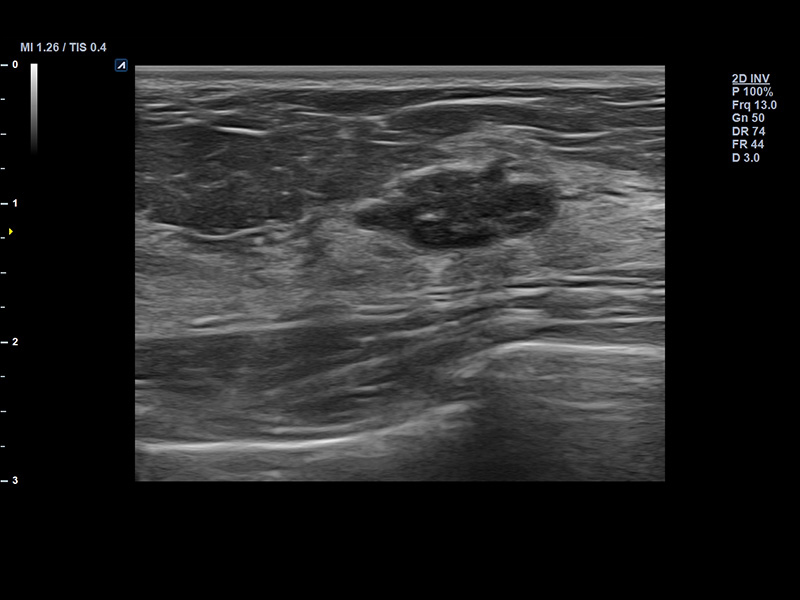

SL3-19H

X+ Crystal Signature™ linear transducer(3~19MHz)

Application:

MSK, Vascular, Small Parts, Breast, TCD, Abdomen, Pediatric, Gynecology, Obstetrics, EM